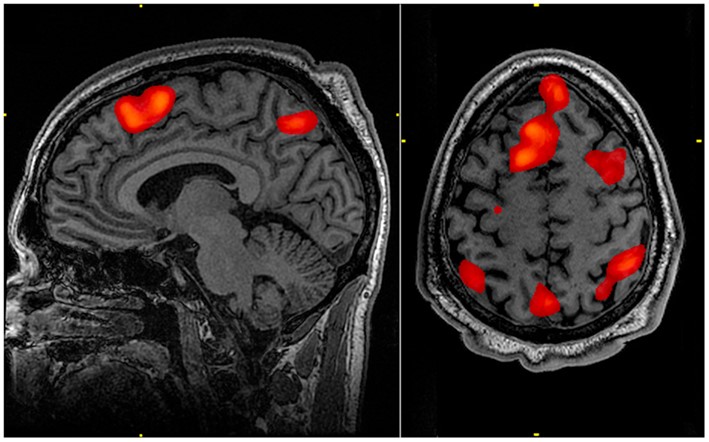

The word ‘functional’ is used as prefix to MRI to indicate when the technology is being used to study a particular function rather than to simply locate atoms. A particular use was discovered in relation to the brain when it was found that the scanner can detect changes in the flow of blood to specific areas of the organ. With advances in processing the tiny signals from the blood vessels in the brain, it is now possible to locate quite precise areas of the brain associated with particular functions. When the nerve cells (or neurons) in these areas are active, blood flows preferentially to them. The resulting signal is processed by a computer which maps the location in relation to the whole brain. Examples of fMRI scans are shown below. The red indicates areas of the brain activated while the subject is using their working memory.

fMRI image of areas of the brain highlighted during a specific mental task